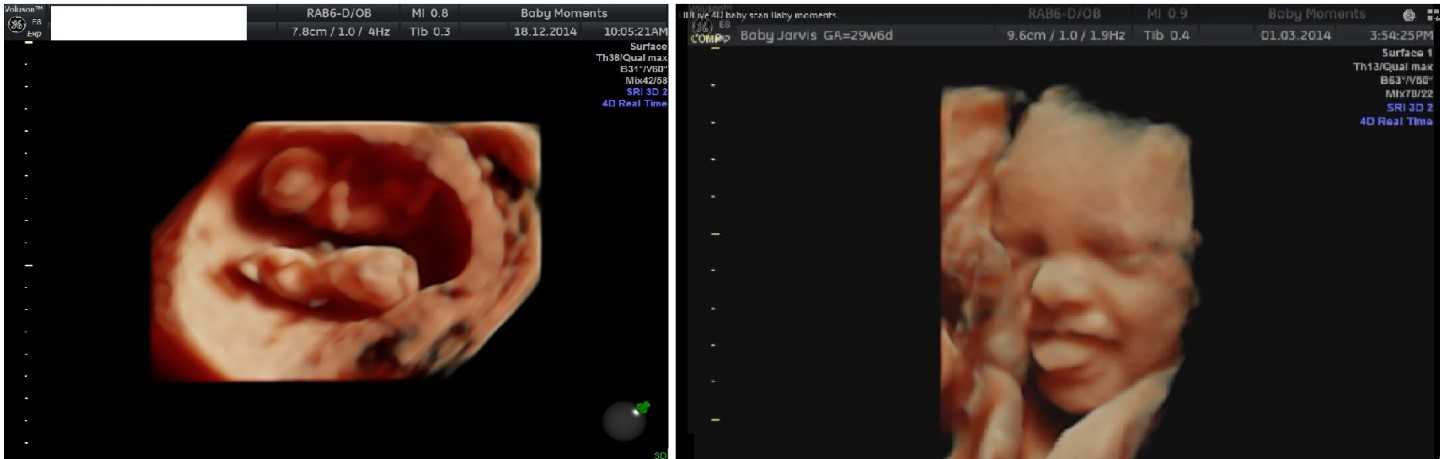

Baby Moments Didcot is a private pregnancy ultrasound clinic in Oxfordshire offering early reassurance scans, gender scans from 16 weeks, 3D/4D bonding scans, and growth wellbeing checks. Parents choose it for detailed insights, emotional bonding, and keepsake images. The clinic provides a calm, family-friendly environment with advanced imaging, flexible appointments, and extras like photos, videos, and heartbeat bears, ensuring a personal and memorable experience. website: https://scan4d.wordpress.com/about-us/ Hastage: #gynecologist near me #nipt test near me #3d scan #cheap early pregnancy scan near me #private pelvic ultrasound

Baby Moments Didcot is a private pregnancy ultrasound clinic in Oxfordshire offering early reassurance scans, gender scans from 16 weeks, 3D/4D bonding scans, and growth wellbeing checks. Parents choose it for detailed insights, emotional bonding, and keepsake images. The clinic provides a calm, family-friendly environment with advanced imaging, flexible appointments, and extras like photos, videos, and heartbeat bears, ensuring a personal and memorable experience. website: https://scan4d.wordpress.com/about-us/ Hastage: #gynecologist near me #nipt test near me #3d scan #cheap early pregnancy scan near me #private pelvic ultrasound #book an early pregnancy scan #ultrasound clinic near me #book baby scan #emergency ultrasound pregnancy near me #gender blood test near me #prenatal scans near me #private reassurance scan near me #baby scan clinic near me #gender scan. #ultrasounds scans #14 week gender scan near me #maternity scanning centre near me #early pregancy scan